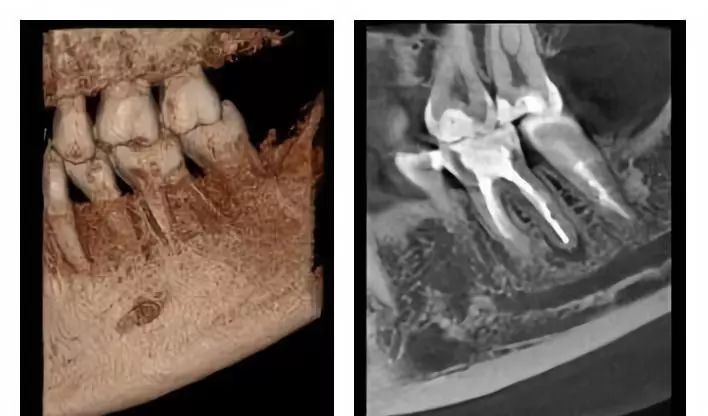

口腔CT是圍繞人體的一段容積螺旋式的采集數(shù)據(jù)。口腔CT與常規(guī)CT的本質(zhì)區(qū)別在于前者獲得的是三維信息,而后者獲得的是二維信息??谇籆T機(jī)提高了掃描速度,掃描覆蓋面廣,無間隙采集容積數(shù)據(jù),便于各種方式、各種角度的影像重建,且可以任意地、回顧性重建。視野選擇與圖像合成方面,口腔CT機(jī)比常規(guī)CT有著明顯的優(yōu)勢。它的空間分辨率高,對下頜骨、下頜神經(jīng)管、顳下頜關(guān)節(jié)解剖結(jié)構(gòu)、牙齒根管系統(tǒng)成像質(zhì)量更好。以下介紹三維口腔CT機(jī)的臨床應(yīng)用特點是什么?

3.成像更加清晰,臨床應(yīng)用更加便捷

通過三維重建并輔以軸位和其它層面圖像,便于醫(yī)生準(zhǔn)確了解埋伏牙,多生牙,囊腫,腫瘤等的形態(tài)、位置、鄰牙及臨近解剖結(jié)構(gòu)的關(guān)系。